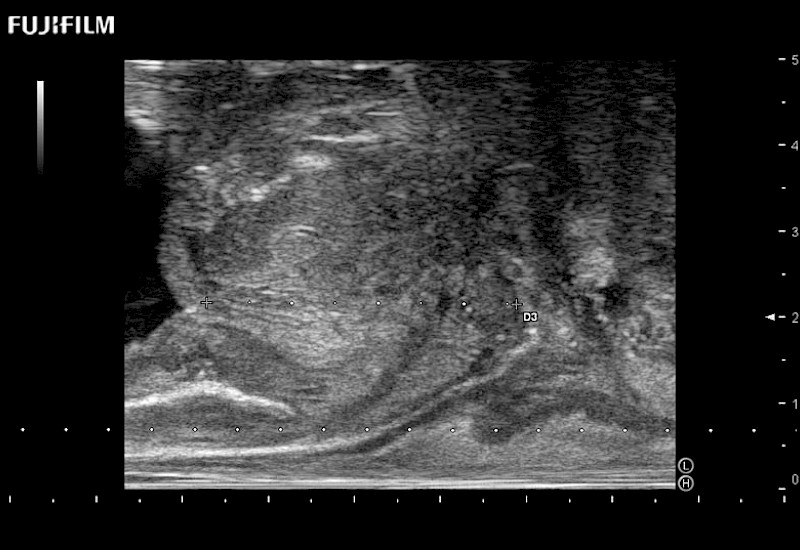

38mm footprint is ideal for scrotal and penile doppler imaging

Main Specifications:

Larger footprint is ideal for scrotal and penile doppler imaging